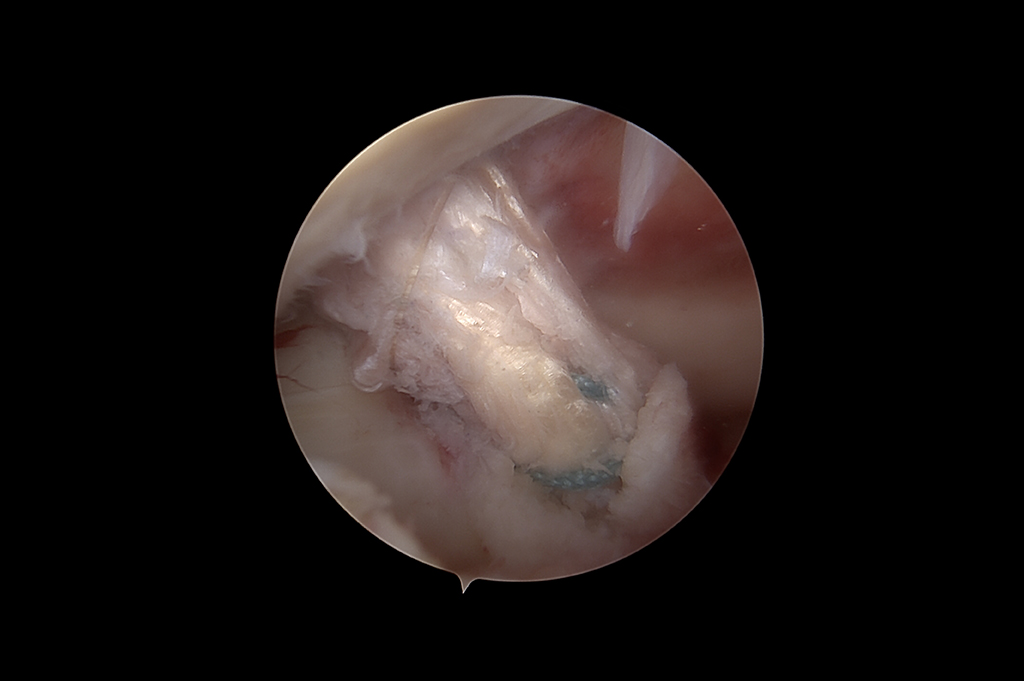

Arthroscopy - ACL Reconstruction, Maniscus Injury